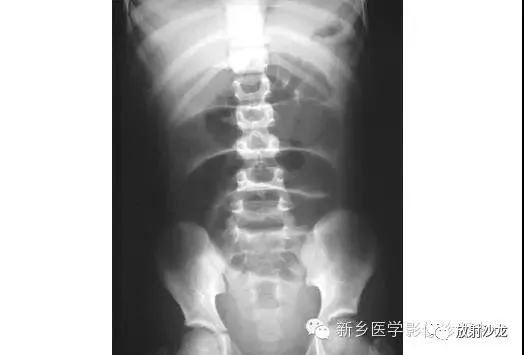

腹部脏器有实质器官和空腔脏器之分,其正常腹平片表现不同。

● 腹平片上实质器官的正常表现:

实质器官:肝、胰、脾和肾等是中等密度,但借助于器官周围或邻近的脂肪组织和相邻充气肠胃的对比,于腹平片上,可显示器官的轮廓、大小、形状及位置。

正位片在部分病人可显示肝下缘,肝下缘与肝外缘相交形成肝角,一般呈锐角。

脾上极与左膈影融合,下极较圆钝。而肾沿腰大肌上部排列。

胰腺于平片上不易显示。子宫偶尔显影,位于膀胱上缘上方呈扁圆形软组织影。

● 空腔脏器在腹平片上的主要表现:

空腔器官:膀胱的脏壁为中、胆囊和肠胃道等密度,依腔内容物不同而x线表现不同。

胃、十二指肠球部及结肠内可含气体,于腹平片上可显示其内腔。小肠除婴幼儿可有积气外,一般充满食糜及消化液,与肠壁同属中等密度,因缺乏对比而不能显示。

如胃内有较多固态食物,结肠或直肠内有较多粪便,因为它们周围有气体衬托,故可显出软组织密度斑片或团块影。

结肠分布于腹部四周。膀胱和胆囊周围有较多脂肪,也可显示部分边缘。